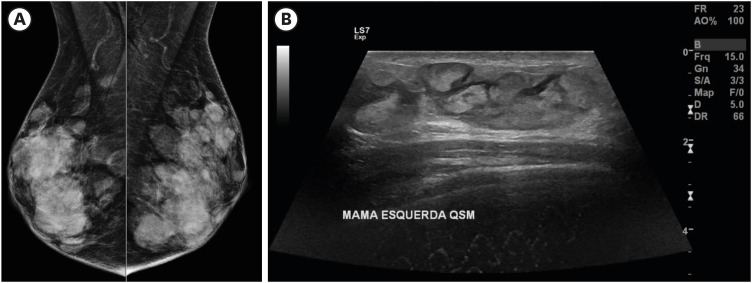

Erdheim-Chester disease (ECD) is a rare multisystem disorder characterized by mitogen-activated protein kinase (MAPK) pathway mutations. Herein, we present a unique case of ECD in a 79-year-old female with predominant breast nodules. Comprehensive imaging and histopathological evaluations confirmed the diagnosis. Mammography and ultrasonography revealed multiple hyperdense circumscribed nodules with coalescing masses and blurred margins. Core biopsy revealed infiltrating foamy cluster of differentiation (CD) 68+ and CD1a+ histiocytes. Because the tumor was negative for the BRAF V600E mutation, treatment with interferon-α was initiated. This case highlights the diagnostic challenges associated with ECD, the rarity of breast involvement, and the importance of considering ECD in the differential diagnosis of atypical breast lesions. Comprehensive imaging, histopathology, and genetic testing are essential for accurate diagnosis and treatment decision-making in ECD. Further research and awareness are required to improve recognition and management of this rare disease.